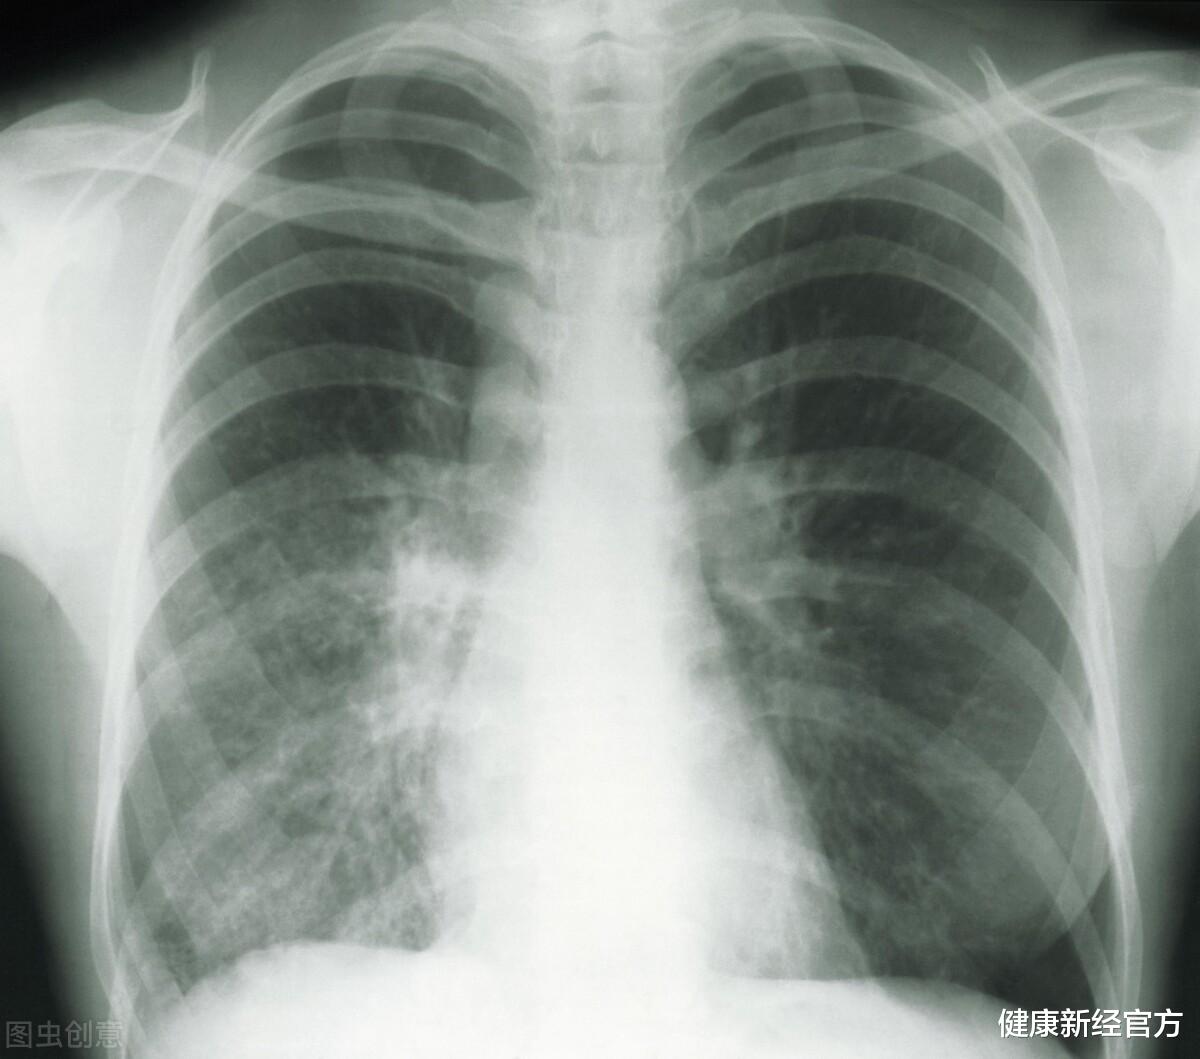

拿到体检报告单后的这几天 , 王先生寝食不安 , 因为报告上有一个结论“右肺上叶前段小结节 , 建议1年后复查” , 肺上长了东西 , 还要让复查 , 医生是不是怀疑恶性?是不是肺癌?完了 , 我患肺癌了 。 这些想法不自觉地就产生了 , 而且越想 , 越觉得自己可能是得肺癌了 。

肺结节引起了相当大一部分人的焦虑 , 那么这个肺结节到底是个什么东西?是癌症吗?首先肺结节不是一种具体的疾病 , 只是一个形态学的描述 , 很多疾病都可以以结节的形势表现出来 。 再者肺结节不等于肺癌 , 95%以上的肺结节都是良性的 。

既然肺结节大部分都是良性的 , 那医生为什么还要让患者复查?因为早期肺癌也是以肺结节的形态展现在我们面前的 , 早期肺癌比较小 , 有时不容易仅凭一次的胸部CT就能判断结节的良恶性 , 需要动态观察 。 恶性结节有生长性 , 在较短的复查期内 , 我们可以观察到肺结节的生长性 , 这就给了医生支持恶性的依据 , 有了确切的证据表明是恶性的 , 那么我们也就可以把结节切掉了 。